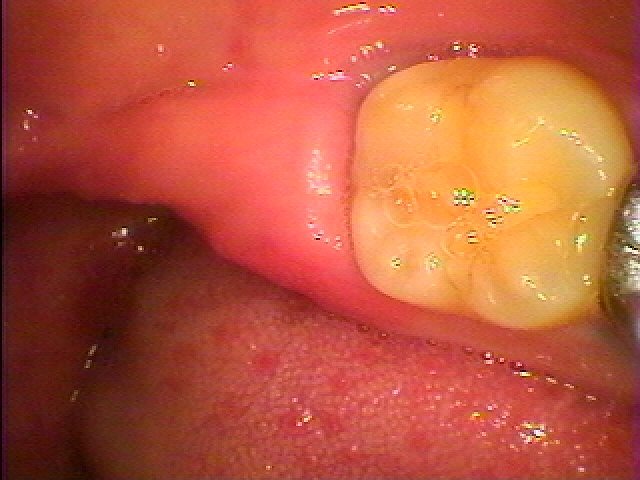

ブログ一覧|広島市安佐南区の歯科医院 ブログ一覧 トップ ブログ一覧 お知らせ スタッフブログ ブログ一覧 お知らせ 2025/02/04 左下の奥 親知らずの難抜歯 水平埋伏歯 お知らせ 2025/02/04 左下の奥がちょくちょく腫れる 親知らずが埋まっているといわれた もう抜きたい お知らせ 2025/02/03 インプラント埋入からかか月が経ちました 2本のインプラントと2本の天然歯に最終ジルコニアクラウンを合わせていきます お知らせ 2025/02/03 前歯部がグラグラする 歯も伸びてきた 診てほしい お知らせ 2025/02/03 右上の1番部のインプラント治療の臨床現場 お知らせ 2025/02/01 インプラント埋入から3か月 傷も落ち着きインプラント部へ歯を建てていきます お知らせ 2025/02/01 左上の6番部が嚙んでも痛む 診てほしい 抜歯から傷がいえるのを待ってインプラント埋入へ お知らせ 2025/01/31 右上の臼歯部のサイナスリフトケース 30代後半女性 << … 5 6 7 8 9 … 435 436 437 438 439 … 870 871 872 873 874 >> Web診療予約 初めての方へ 選ばれ続ける理由 院内設備について 歯が痛いしみる一般歯科 歯がぐらぐらする歯周病 健康な歯を保ちたい予防歯科 子供の虫歯予防をしたい小児歯科 銀歯をセラミックに審美歯科 白い歯を目指しませんか?ホワイトニング 矯正専門医がいるので安心矯正歯科 抜けた歯を補いたいインプラント・入れ歯 医院案内 スタッフ紹介 メリィハウス歯科クリニックオフィシャルホームページ ラベンダー歯科クリニックオフィシャルホームページ お知らせ・ブログ ホーム 診療科目 一般歯科 歯周病治療 予防治療 小児歯科 審美治療 ホワイトニング 矯正歯科 入れ歯・インプラント マウスピース矯正 初めての方へ 院長・スタッフ 設備紹介 医院案内・アクセス メニューを閉じる